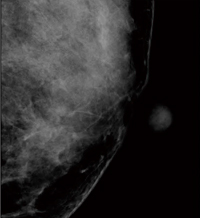

■症例1:spiculated massの検出

症例1:2D画像(所見部分拡大) |

症例1:トモシンセシス静止画像 |

症例1:左CCの2D画像 |

症例1:左CCのトモシンセシス静止画像(19スライス目) |